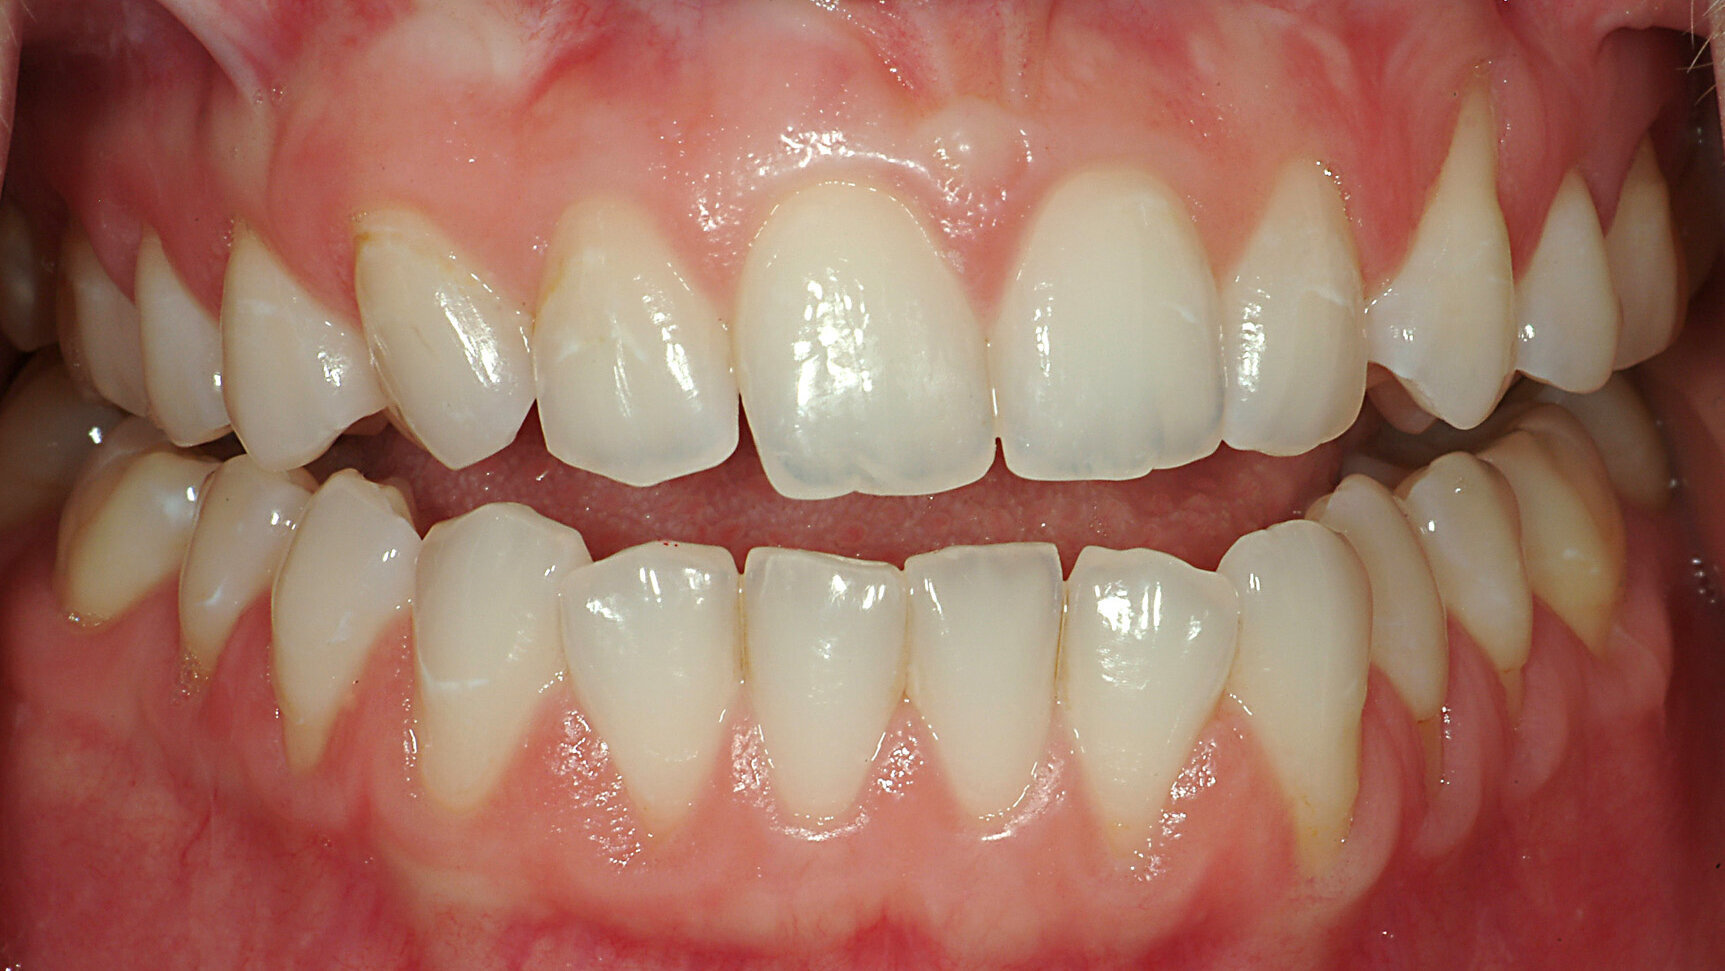

Fig. 20a: Digital recording of intercuspation.

Fig. 20b: Digital recording of intercuspation.